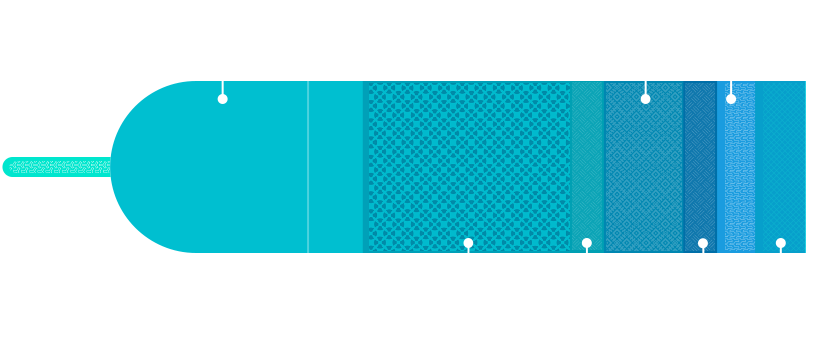

先进探头技术

IBS探头技术

I:Increase Matching Layers,匹配层+,增加匹配层至三层,更好的提升探头的灵敏度和带宽;

B:Bonding Process,邦定加工技术,通过均匀粘接工艺,连接陶瓷和电极的胶层厚度控制在最大1um以内,以改善阵元间的性能一致性;

S:Super Elements,超级阵元,通过超精密加工,一个阵元被分为若干子阵元(最小尺寸为75um)以增加探头的灵敏度和带宽;

以上三种简称IBS探头技术

IBS技术使得探头灵敏度和带宽均提高40%,一致性提升37%,长期稳定性提升42%